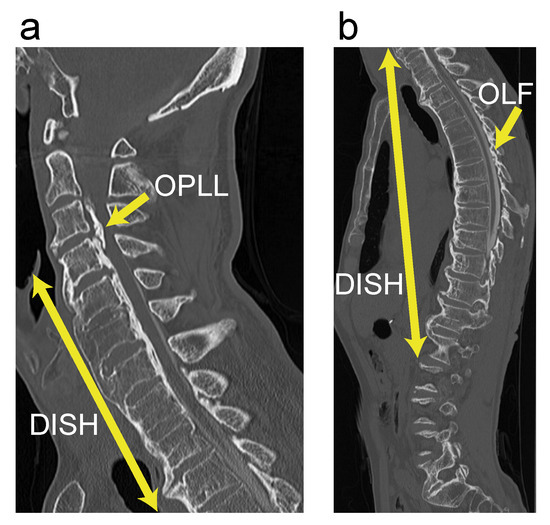

3.3. Case Presentation